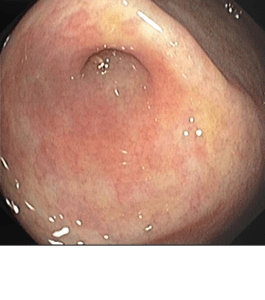

La ligadura endoscópica de várices esofágicas es un procedimiento terapéutico utilizado para tratar las dilataciones varicosas en el esófago, una complicación común de la hipertensión portal, especialmente asociada con la cirrosis hepática.

Durante la ligadura endoscópica, se utiliza un endoscopio flexible para guiar el paso de una liga de látex alrededor de las várices esofágicas. Esta liga de látex se coloca en la base de las várices, lo que provoca su estrangulamiento y eventual necrosis (muerte tisular). Este proceso reduce el riesgo de ruptura y sangrado de las várices, proporcionando un tratamiento efectivo para prevenir complicaciones graves como la hemorragia digestiva.